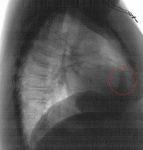

Пол пациента: Женский пол Тип патологии: Другое Область исследования: Грудная клетка и верхние дыхательные пути Методы исследования: Rg Женщина 30л. Диагностическая флюорография. За 4 ребром справа овальная тень? Дисковидный ателектаз? Ваше мнение коллеги? ID:78936 Цель публикации: Консультация Wed, 14/11/2018 - 21:14 #1 Игорь Ким Offline Last seen: 1 year 5 months ago Joined: 17.10.2014 - 17:30 Posts: 4672 Не ателектаз. Уплотнение добавочной междолевой. Wed, 14/11/2018 - 21:24 #2 И.Бондаренко Offline Last seen: 21 hours 43 min ago Joined: 13.09.2011 - 22:55 Posts: 9208 Игорь Ким wrote: Не ателектаз. Уплотнение добавочной междолевой. Возможно малый плеврит. Wed, 14/11/2018 - 21:37 #3 NIL Offline Last seen: 1 month 1 week ago Joined: 25.11.2013 - 20:50 Posts: 18208 Игорь Ким wrote: Уплотнение добавочной междолевой. +1 "Слушай всех, прислушивайся к немногим, решай сам".© Thu, 15/11/2018 - 06:21 #4 Оськин С.В. Offline Last seen: 2 years 4 weeks ago Joined: 07.04.2016 - 17:05 Posts: 1703 Коллеги, как вы оцениваете эту тень? У меня затрунение вызвала. Приложения:

Коллеги, как вы оцениваете эту тень? У меня затрунение вызвала.